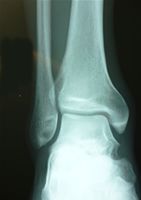

痛みが長引くようでしたら X線分析が必要でしょう。

足関節と主な筋群と神経支配の関係

前脛骨筋・長趾伸筋・長母趾伸筋・長腓骨筋・ヒラメ筋・アキレス腱・短、長趾屈筋・頭母趾屈筋・後脛骨筋・側底筋等

40年来病院勤務(放射線科)、体の障害による痛み、スポーツ障害、事故等、

40年来病院勤務(放射線科)、体の障害による痛み、スポーツ障害、事故等、

患者さんのX線検査、慢性的な後遺症等々に携わり、どんな小さな体の障害でも長年に渡り各関節・筋肉・靭帯に影響を及ぼす事が判りました。

『捻挫』『肉離れ』『骨折』『関節障害』等、早期に異常箇所を見つけて正常組織に改復しなければなりません。

私はたかが捻挫されど捻挫と重要視しています。

足の捻挫は複雑でやがて全身の関節に影響が及ぶ事があり、変形性関節症に移行する事もあります。

早期にどの筋が短縮しているのか、関節内、靭帯、軟骨なのか、痛みの原因を見つけ出さなければなりません。